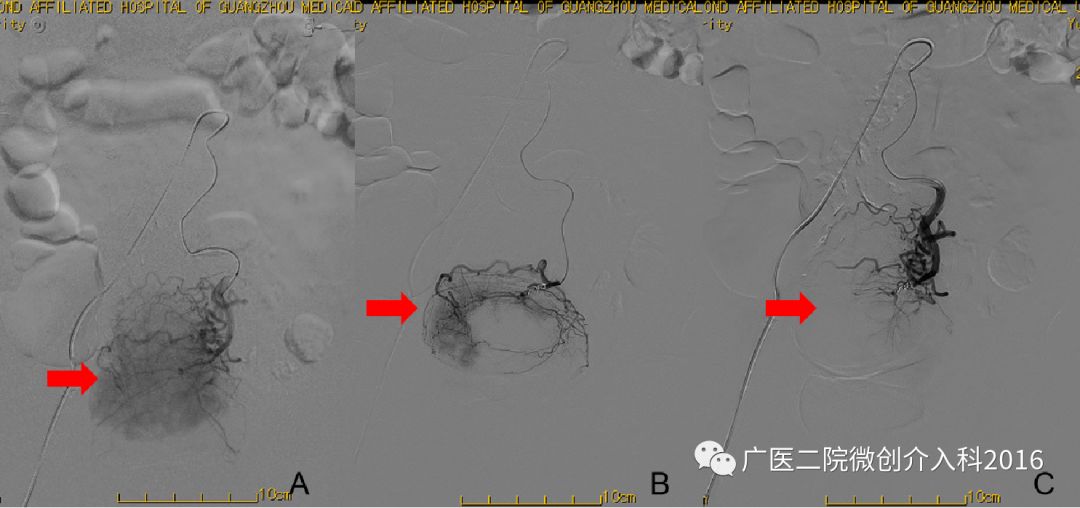

患者为十二指肠溃疡并大出血,经内科药物治疗效果不佳,仍有大量出血,生命垂危。图A、B行十二指肠动脉造影,可见造影剂浓聚和外渗,精准找到出血部位和责任血管。通过注入弹簧圈堵塞出血血管,图C再次造影可见原出血征象消失,患者出血停止。经后续治疗,患者脱离生命危险。

病例3:胆道出血

患者为经皮胆道取石术后胆道出血,经内科药物治疗无效,仍有大量出血。图A行肝动脉造影,右肝可见造影剂外溢并呈囊状扩张,表示正在出血。图B行介入栓塞治疗,注入不同规格的弹簧圈行出血动脉栓塞术。图C再次造影可见原出血征象消失,患者胆道出血停止。